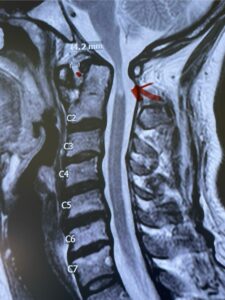

Fig. 4a: Sagittal T2-weighted cervical MRI demonstrating severe cord compression with myelomalacia of upper cervical spinal cord (red arrow). Notice the increased atlanto-dens interval (red dot).

Cervical x-rays revealed a significantly increased atlanto-axial interval (Fig. 5) On review of her imaging studies it was noted that the right C2 isthmus was very thinned by the vertebral foramen (Figs 6a, b, and c) which would make an attempt at placing a C2 pars screw dangerous. A decision was made to perform an occipital-cervical fusion because only possible unilateral fixation and an extensive C1 laminectomy to be performed eliminating a fixation point if a more traditional C1-C2 was performed. Even if C1 lateral mass screws were able to be placed one could only perform a unilateral screw construct fixation to C2. We performed an occipital cervical fusion down to C4 to get enough inferior fixation and C1 laminectomy. The decompression went well. We placed a left unilateral pars screw and bilateral C3 and C4 lateral mass screws. We placed three 12 mm screws in the midline keel (Fig. 7). Postoperatively the patient had all around improvement in her symptoms and did not qualify for rehab. Her post op films at 6 weeks (Fig. 8)